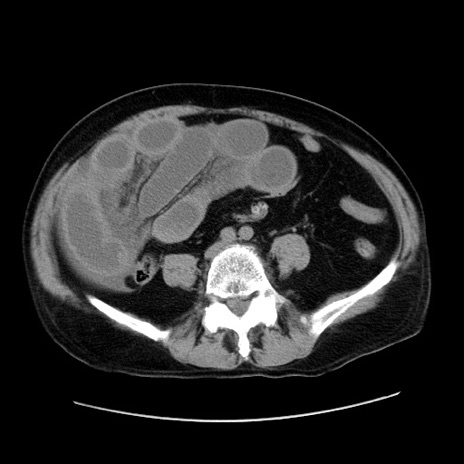

症例30(横断像)

【症例】80歳代男性

【主訴】臍周囲痛

【現病歴】約6時間前から臍下部痛が出現。次第に腹部膨隆・背部痛も生じてきたため来院。背部痛の場所は変化しない。

【身体所見】意識清明、BT 36.3℃、BP  131/87mmHg、P 87bpm、SpO2 100%(RA)、臍周囲自発痛・圧痛あり、反跳痛なし、自発痛部位に一致して板状硬あり、腹部膨隆、腸雑音減弱、CVA tenderness両側陰性。